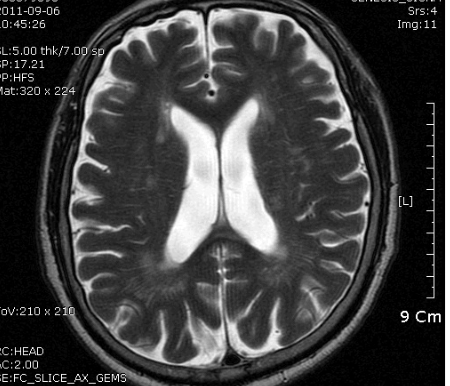

PCA terrotory infartion + AchA territory

B MRI 촬영 결과는 좌측의 corona radiata, Lt temporo-occipital lobe 의 subcortical area 의 optic radiation 부위를 비롯한 여러 군데 점상 병변. N/S 정주하고 Aspirin 투여 시작, 혈압약은 지속 투여, SBP 160정도로 유지.

촬영 결과는 좌측의 corona radiata, Lt temporal lobe는 anterior choroidal artery 영역입니다.

한병인: Stroke 4ed p174 에, PCA영역의 infarction은 MCA영역의 그것과 달리 subcortical compartment를 많이 침범한다고 함.

따라서 borderzone 은 아니고, PCA 영역의 artery to artery embolic stroke 일 가능성이 높다고 생각함.

좌측사진은 PCA 영역. 우측사진은  AchA 영역의 post. periventricular corona radiata (Stroke 4ed p199, Fig 9-3 과 동일)

DWI coronal or saggital view 보면 분명하겠지만 이 사진으로 보니 PCA territory infarction으로 모두 설명되는 것 같습니다. PCA 영역에 hypoperfusion으로 병변이 크지는 것 같습니다. 5-7일 지나야 안정기에 들어갈 것 같습니다.